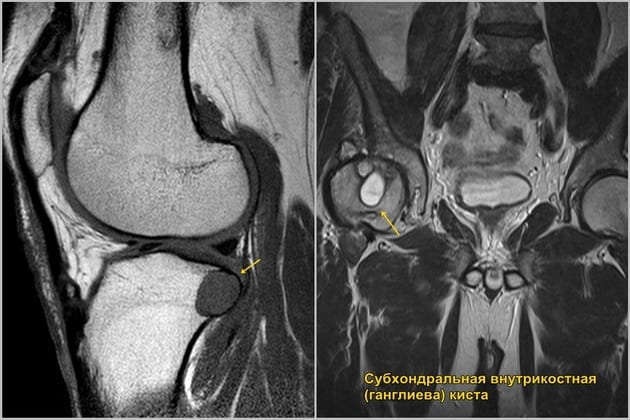

- субхондральная киста. Является доброкачественным новообразованием небольшого размера — от 0,5 до 1,5 см. Возникает у людей, в старости имеющих дегенеративно-дистрофическое поражение суставов. Образовывается из фиброзной ткани и сопровождается дегенеративными модификациями хряща;

- ганглиевая киста. Довольно редкий тип патологии возникает из сухожильной области. Она является доброкачественной и представляет собой образование овального вида с протокой посередине. Наполнена киста прозрачной жидкостью, определить причину проявления патологии тяжело: как правило, она обнаруживается у юных девушек, имеющих гипермобильность суставов.